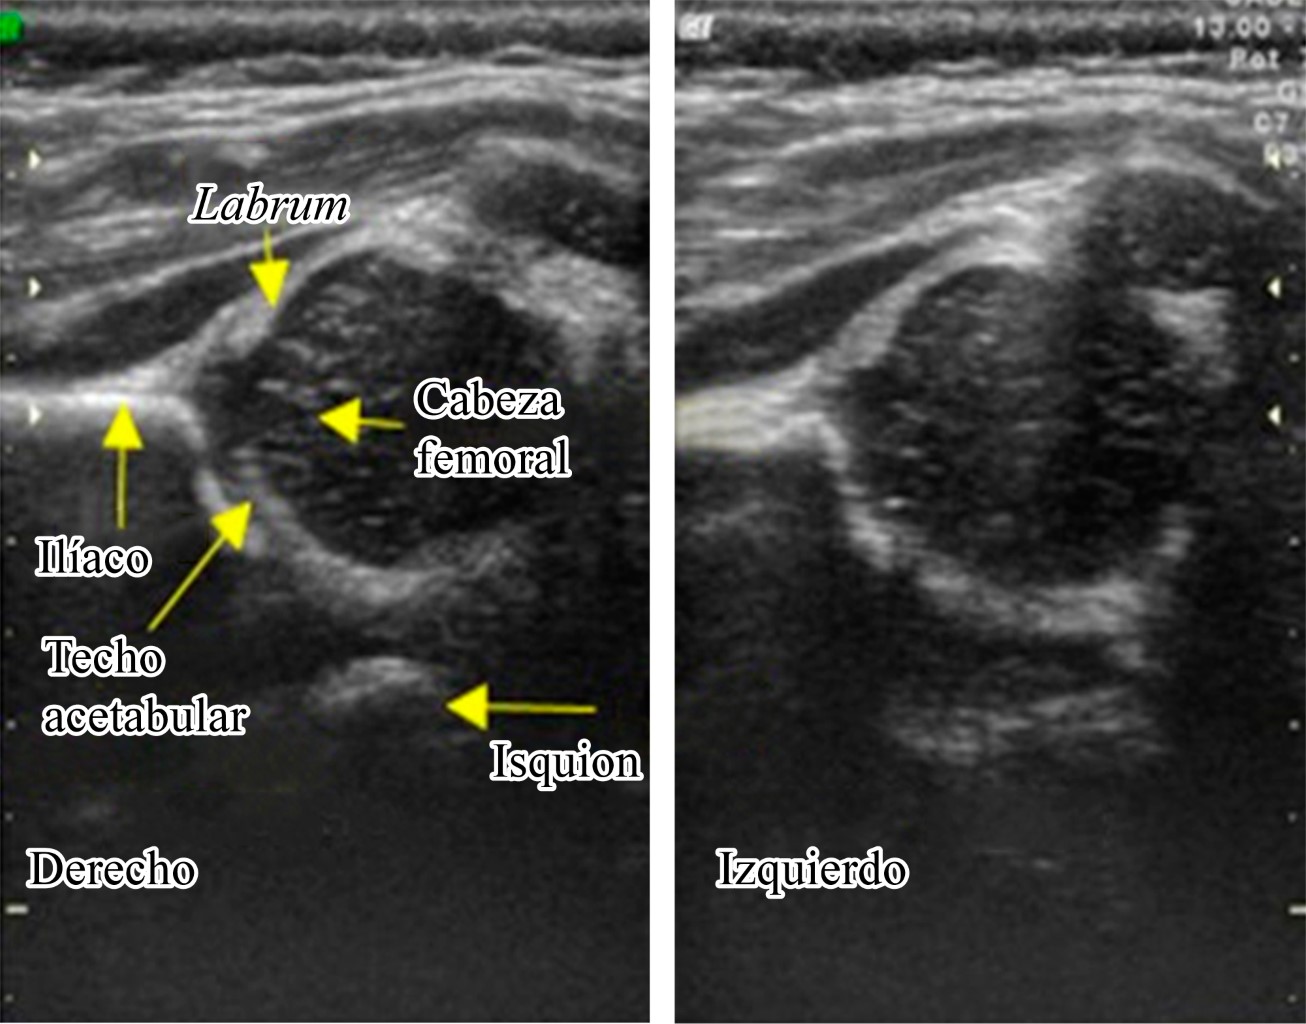

Application of the Graf method for diagnosis and early detection of hip dysplasia

Introduction: Developmental hip dysplasia (DHD) is the most common disorder affecting pediatric hip; screening all neonates clinically, and using ultrasonography selectively for those babies who are at high risk is a widespread recommendation. our goal is to evaluate the impact that USG diagnosis and early treatment of DHD has had on the child population of our unit. Material and methods: Retrospective, descriptive and cross-sectional study. Records of those children from one to six months of age, with a diagnosis of DHD, without distinction of sex, subjected to ultrasonographic tracking in the period from January 2018 to December 2019 were reviewed. A follow-up of six months was carried out in all patients, from the moment of diagnosis and the start of treatment with harness, weekly visits for relocation, as well as ultrasonographic revision every four weeks to monitor the treatment. Results: 19 cases were reported from the left side (47.5%), 10 cases from the right side (25%) and 11 bilateral cases (27.5%). The main associated risk factors were: product of the first pregnancy, family history of DHD, pelvic presentation, female sex. The results were favorable with a continuous use of harness of 23 hours observing a satisfactory evolution in 99.2% of the patients. Conclusion: With the results obtained we can analyze the considerable success rate of the hip clinic of our hospital with the realization of the ultrasound, we find a lower incidence of patients with pain, limitation of function, as well as satisfactory gait patterns.

Figure 1

Figure 2